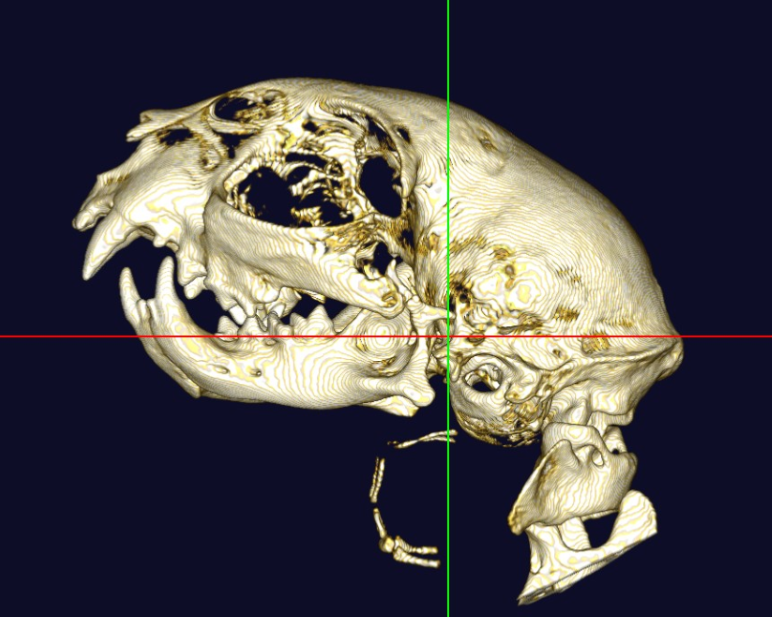

高画質で立体的に見ることで、レントゲンや超音波検査では分からない病態の診断や、構造が複雑な部位の細かい評価が可能です。

体の断層像に加え立体3D画像の作成が可能

事前に病変部位やその周囲の臓器との関係性を把握することで、より正確で安全な外科手術につながります。

また、飼い主様へお話しする際に、立体の3D画像のため病変のイメージがしやすくなります。

猫 頭部CT